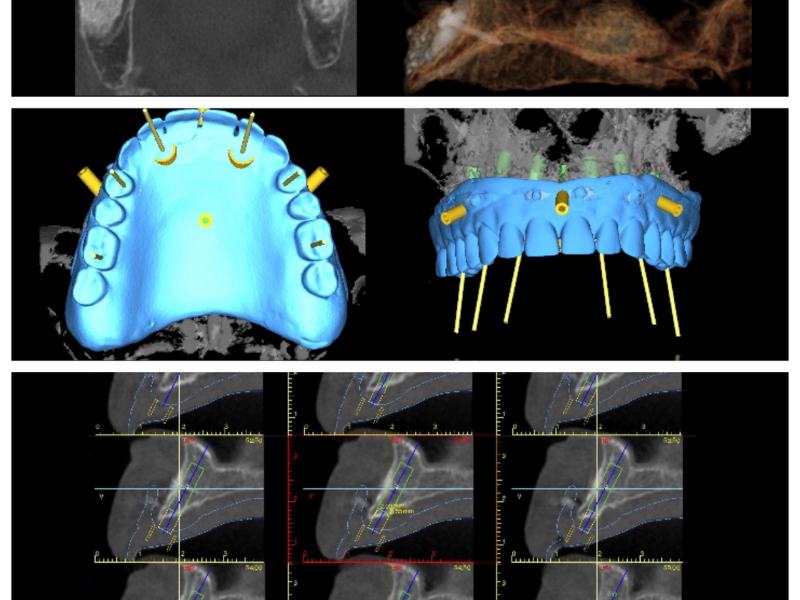

O sistema de navegação de Cirurgia Guiada é composto por vários dispositivos que permitem que o cirurgião monitore a localização de instrumentos cirúrgicos no corpo do paciente durante o procedimento cirúrgico. Estes dispositivos incluem sensores de movimento, imagens de raios-X, ultrassom e até dispositivos laser. A Cirurgia Guiada permite que o cirurgião use um monitor para visualizar e acompanhar a localização de instrumentos cirúrgicos dentro do corpo do paciente.

Além da precisão, a Cirurgia Guiada também proporciona ao cirurgião um melhor entendimento da anatomia do paciente. Isso é possível graças ao uso de imagens de raios-X ou ultrassom durante o procedimento, o que permite que o cirurgião visualize o interior do corpo do paciente. Isso torna possível para o cirurgião localizar com precisão estruturas anatômicas específicas e evitar áreas sensíveis.